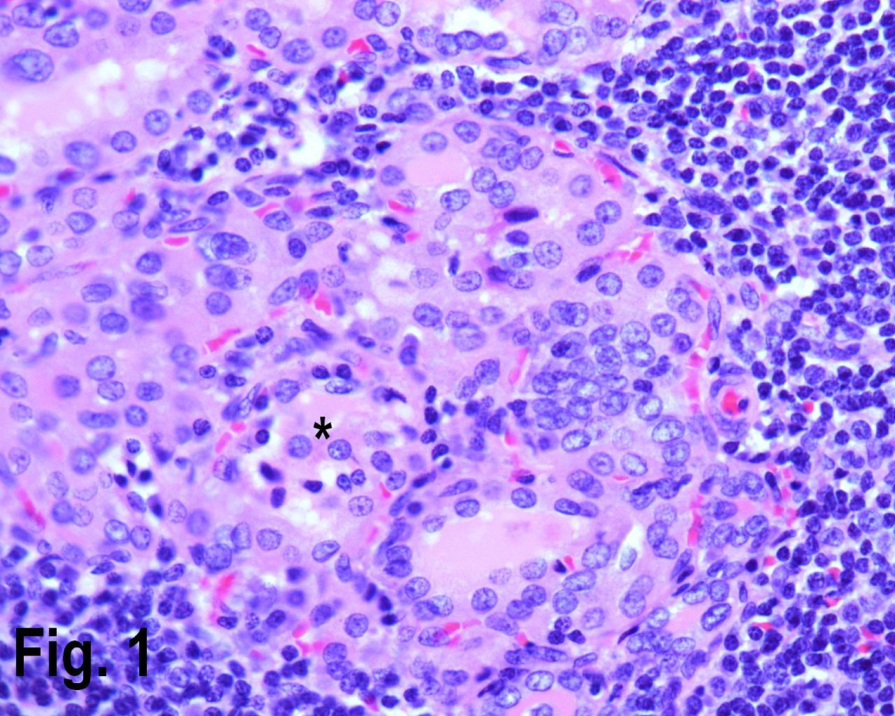

Figure 1.High power view showing Hashimoto’s thyroiditis with lymphocytic infiltrate in the periphery and Hurthle cells {asterisk} in the center. (Hematoxylin & eosin, original magnification ×400).

Total number of thyroidectomies performed in our institution over a nine years period was 256, of which 171 cases were non neoplastic, 85 neoplastic; of those 23 cases were adenomas and 62 cases were malignant (Table 1). The non neoplastic lesions (multi nodular goiter and auto immune thyroiditis) peak frequency was in third to fifth decades (Table 2). The youngest patient in our series was twelve years male with colloid nodule. The age ranged from 12 years to 78 years. Of the total non neoplastic lesions, there were 142 females constituting 80% in this series and the male to female ratio was 4:1. Female accounted for 99 cases (80%) of the multi nodular goiter, 14 cases (93%) of goiter and thyroiditis, 20 cases (95.2%) of Hashimoto’s thyroiditis (Figure 1) and 8 cases (80%) of colloid nodule.